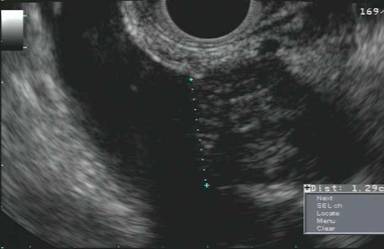

Following a visit to the University of Colorado Multidisciplinary Gastro-Intestinal Tumor Clinic, the patient underwent neo-adjuvant chemotherapy with 3 months of FOLFIRINOX followed by restaging. Repeat pancreas protocol CT scan showed a decrease in the size of the entire pancreas with both masses (head and tail) also decreasing in size. A total pancreatectomy was offered and performed (Figure 3). Segmental superior mesenteric vein resection was also done with an end to end anastomosis, as the tumor came within less than 1 millimeter from the retroperitoneal margin on frozen section. The postoperative course was uncomplicated and the patient was discharged home on day 7. The final pathology demonstrated two discrete tumor masses, 5.0 cm and 4.5 cm, with extensive colonization of the intervening pancreatic duct. On histology, the tumor consisted of sheets of undifferentiated carcinoma cells separated by dense fibrosis. Clusters of multinucleated foreign body-type giant cells, associated with cholesterol clefts and other degenerative features, were present in the stroma adjacent to the tumor cells. These were interpreted as neoadjuvant treatment effect and not as native component of the tumor (Figure 4). All margins, including the superior mesenteric vein segment, were negative for malignancy; three of 28 lymph nodes contained metastatic deposits. Immunohistochemical staining was positive for pancytokeratin AE1:AE3, CA 19-9 and patchy positive for B72.3, negative for chromogranin and synaptophysin and equivocal for CEA. Final pathologic staging was pT3N1M0.

Figure 3. Total pancreatectomy/splenectomy specimen. |